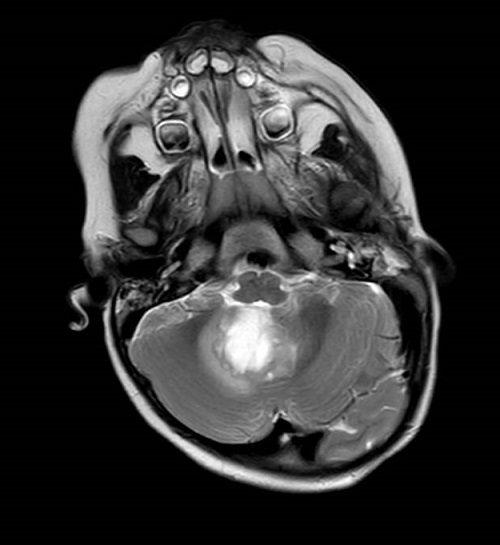

Se realiza una prueba de imagen a los 23 meses de edad, en la que se evidencia una lesión focal intraaxial en la fosa posterior que afecta al cuarto ventrículo, sugestiva de neoformación primaria compatible con ependimoma o glioma de bajo grado (Low Grade Glioma, LGG) (Figura 2, Figura 3 y Figura 4).

Figura 2. Imagen de resonancia magnética en corte axial donde se visualiza la lesión de fosa posterior con afectación del 4.º ventrículo, con intenso realce de contraste de 2,8 x 2,3 x 2,6 cm. Edema periférico moderado. Mostrar/ocultar